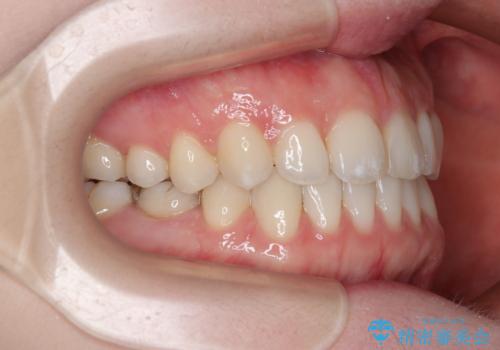

すきっ歯をインビザラインできれいな歯並びに改善

- 前歯の隙間を気にして来院された患者様です。

隙間や叢生の程度はそれほど著しいものではなかったので、インビザラインでもワイヤー矯正でも対応可能でしたが、極力目立たない装置を希望されたため、インビザラインにて矯正治療を行うこととしました。

すきっ歯の原因は色々ありますが、嚥下や発音時の舌突出癖が大きな原因となることがあります。

こちらの患者様も強い突出癖があったため、舌のトレーニング指導を行いました。